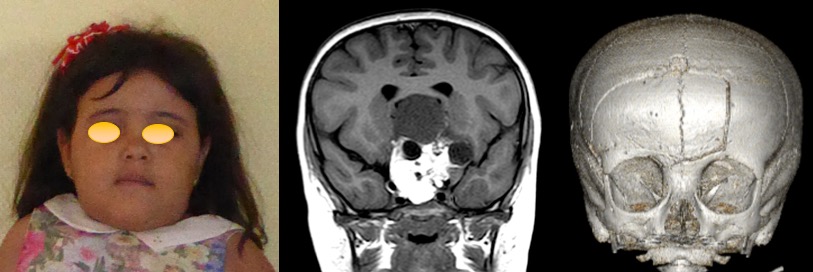

le métopisme est retrouvé également dans certaines conditions malformatives, en particulier en association avec des pathologies de la ligne médiane.- fistule dermique dorso-nasale.

- encéphalocèle ethmoïdale

- fente faciale

stickler syndrome, also associated with Chiari malformation - kyste arachnoïdien supra-sellaire

- tératome supra-sellaire